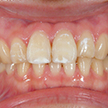

5. 施術前正面観

この患者様に関しての口腔内写真は、この段階から撮らせていただきました。初診時に撮っていれば良かったと痛感しています。